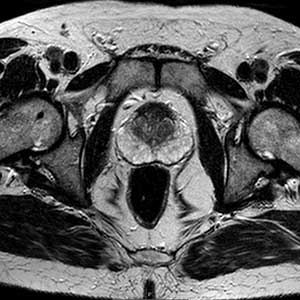

A Ressonância Magnética da Próstata é um exame de imagem não invasivo que oferece imagens detalhadas da próstata e áreas ao redor. Este exame é fundamental para detectar precocemente o câncer de próstata, monitorar a evolução de outras condições prostáticas e auxiliar no planejamento de tratamentos.

A ressonância magnética (RM) da próstata utiliza campos magnéticos e ondas de rádio para criar imagens detalhadas da glândula prostática. Ela é particularmente útil para identificar áreas suspeitas de câncer, bem como para avaliar inflamações, hiperplasia prostática benigna (aumento da próstata) e outras anomalias.

Esse exame é especialmente importante em casos de suspeita de câncer de próstata após exames de sangue como o PSA (antígeno prostático específico) elevado ou uma biópsia inconclusiva. A RM permite um mapeamento preciso da próstata, facilitando diagnósticos mais assertivos.